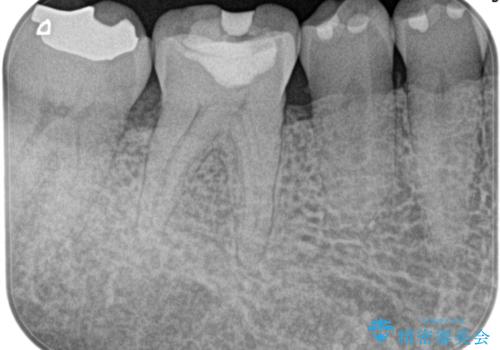

- 1週間前から冷たいもので強い持続痛を感じることを主訴に来院されました。

歯髄診断と痛みの再現により原因歯を特定し、症候性不可逆性歯髄炎の診断となりました。

根管治療〜オールセラミッククラウン(エクセレント)の治療を行なっております。